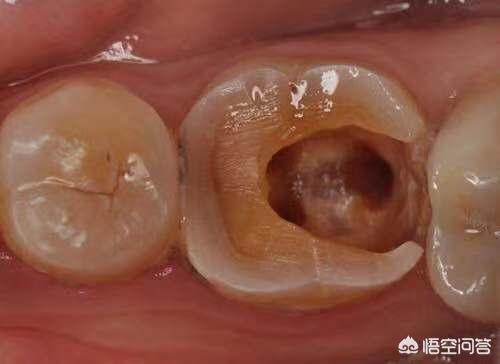

牙齿一旦出现了牙髓病变,就要做根管治疗。牙齿变色是因为坏死牙髓里的血红蛋白发生变性,红色素沉积在牙本质小管内,使我们的牙齿变灰变黑,跟带牙套没有关系。做了根管治疗,牙齿没有了血管、神经的营养,脆性变大,所以,医生通常都会建议患者做牙套。

有可能是内冠材料引起,比如镍铬合金,这种是最便宜的,由于镍离子不稳定,会大量沉积在牙龈边缘,导致牙龈看起来黑黑的,不太美观,至于牙齿也会发黑,因为根管治疗后没有了牙神经,失去营养来源,牙齿逐渐变灰,会变得很脆,就得装牙套保护。

牙齿发黑不应该归咎于牙套,做完根管治疗的牙齿时间久了都会发生变色。这是因为血红蛋白被细菌分解的产物进入牙本质小管引起的颜色变化。烤瓷牙引起的变色多是对牙龈的染色。